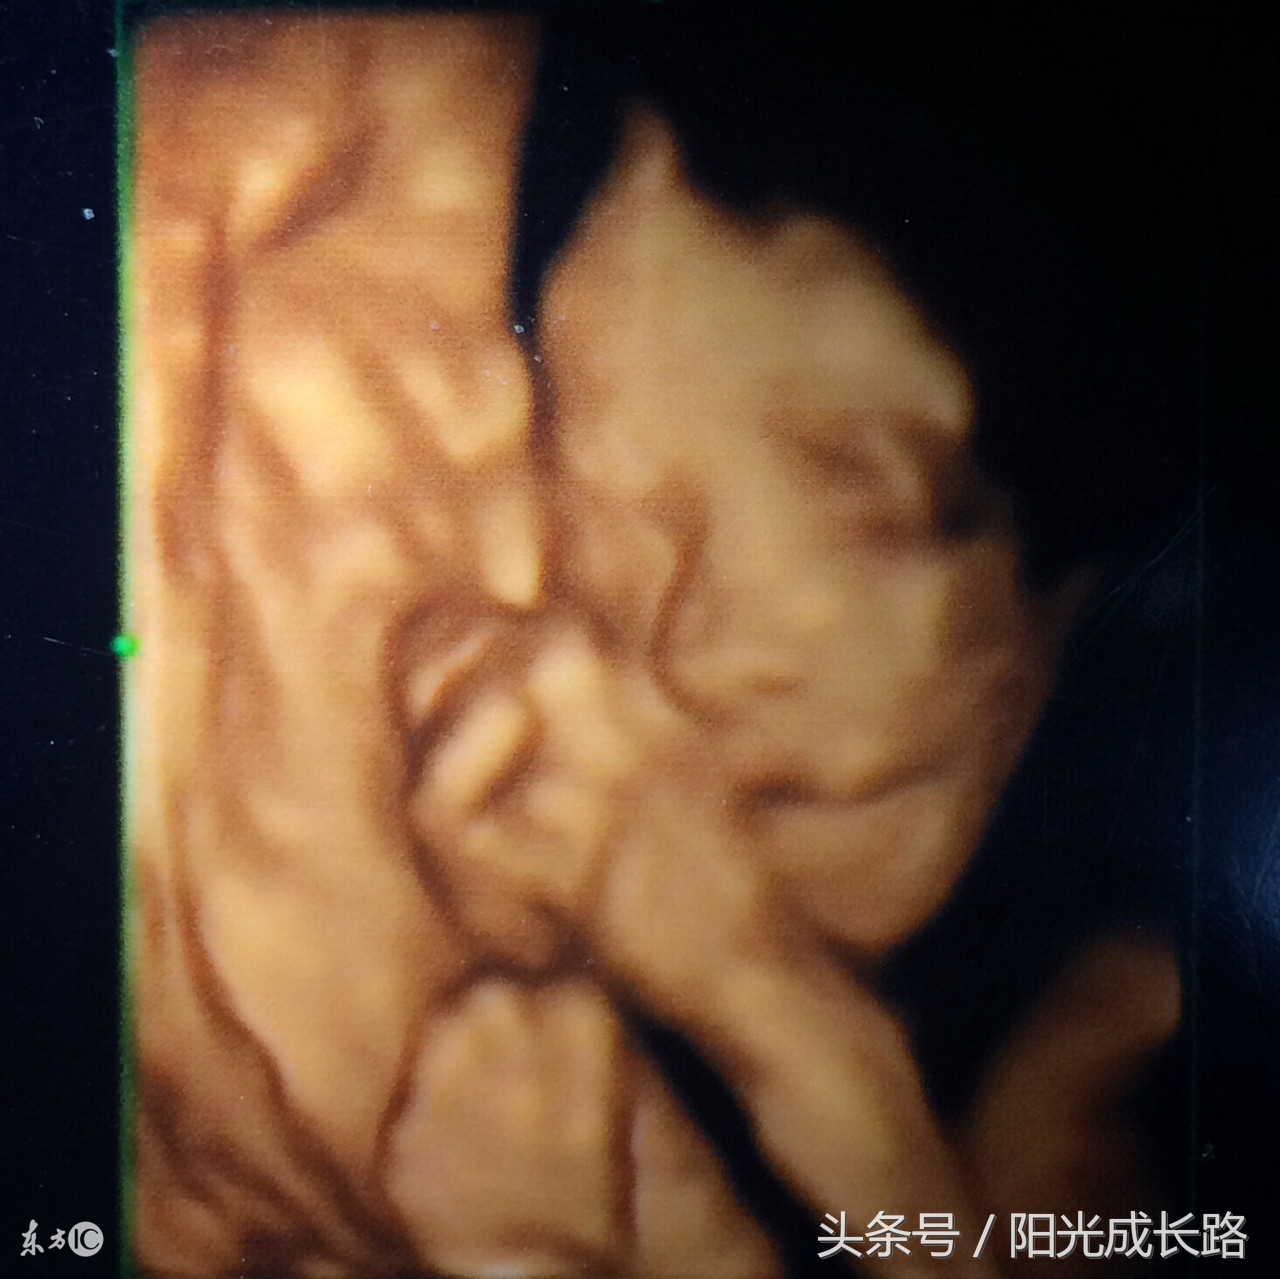

成像不同

系统彩超是二维成像,平面的。四维彩超是立体成像,立体的。